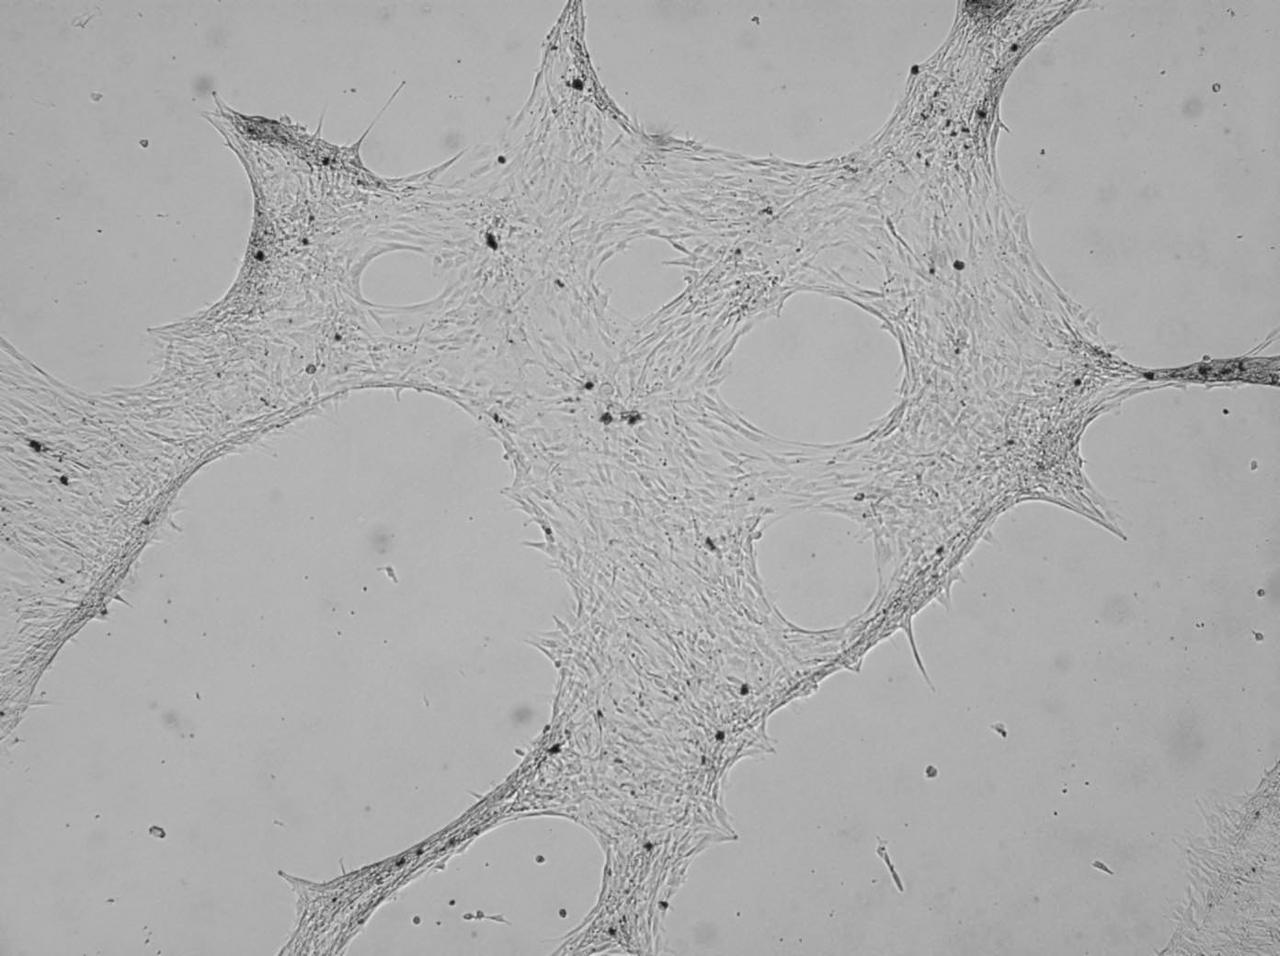

Biomedical research offers hope for a variety of medical problems, from diabetes to the replacement of damaged bone and tissues. Bioreactors, which are used to grow cells and tissue cultures, play a major role in such research and production efforts. Cell culturing, such as this bone cell culture, is an important part of biomedical research. The BioDyn payload includes a tissue engineering investigation. The commercial affiliate, Millenium Biologix, Inc., has been conducting bone implant experiments to better understand how synthetic bone can be used to treat bone-related illnesses and bone damaged in accidents. On STS-95, the BioDyn payload will include a bone cell culture aimed to help develop this commercial synthetic bone product. Millenium Biologix, Inc., is exploring the potential for making human bone implantable materials by seeding its proprietary artificial scaffold material with human bone cells. The product of this tissue engineering experiment using the Bioprocessing Modules (BPMs) on STS-95 is space-grown bone implants, which could have potential for dental implants, long bone grafts, and coating for orthopedic implants such as hip replacements.

Biomedical research offers hope for a variety of medical problems, from diabetes to the replacement of damaged bone and tissues. Bioreactors, which are used to grow cells and tissue cultures, play a major role in such research and production efforts. Cell culturing, such as this bone cell culture, is an important part of biomedical research. The BioDyn payload includes a tissue engineering investigation. The commercial affiliate, Millenium Biologix, Inc. has been conducting bone implant experiments to better understand how synthetic bone can be used to treat bone-related illnesses and bone damaged in accidents. On STS-95, the BioDyn payload will include a bone cell culture aimed to help develop this commercial synthetic bone product. Millenium Biologix, Inc. is exploring the potential for making human bone implantable materials by seeding its proprietary artificial scaffold material with human bone cells. The product of this tissue engineering experiment using the Bioprocessing Modules (BPMs) on STS-95 is space-grown bone implants, which could have potential for dental implants, long bone grafts, and coating for orthopedic implants such as hip replacements.